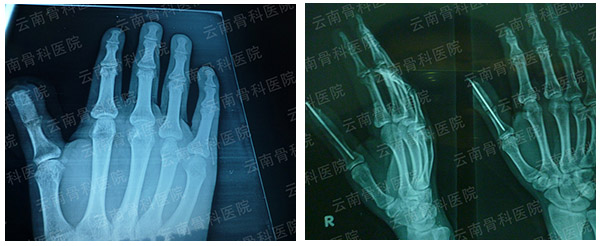

拇指Ⅰ度再造(1)

拇指Ⅰ度再造(2)